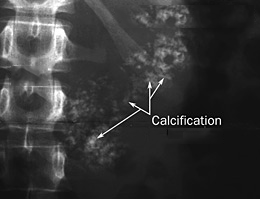

L'abdomen sans préparation peut montrer des calcifications pancréatiques (Figure n°1).

Le scanner est l’examen de première intention et de référence. La phase sans injection permet de faire le diagnostic de calcifications pancréatiques. Il montre les complications comme les pseudokystes (

Figure n°2).

Figure n°1 et 2 : Calcifications pancréatiques sur un ASP et un Scanner